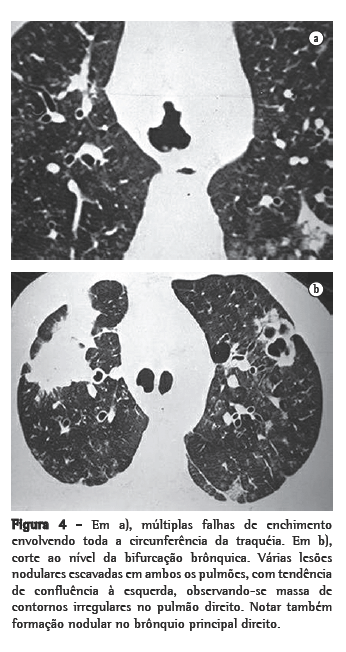

Nos 8 casos foram observadas na TC formações polipóides na traquéia. Em 1 deles, identificou-se também uma lesão em brônquio principal. Sete pacientes mostravam comprometimento do parênquima pulmonar. Em todos foram observadas lesões nodulares escavadas, com contornos internos irregulares, e paredes de espessuras variadas, com aspecto multilobulado em 6 casos, e com confluência das lesões em 5 deles (Figuras 1 a 5). Nódulos sólidos foram vistos em 6 pacientes, Em apenas 1 dos casos foram vistos níveis líquidos. As lesões predominaram nas bases em 3 pacientes, nos terços médios em 2, e em 2 não havia predomínio de distribuição. Em 1 dos pacientes, foi observada associação com massa, e em outro, com consolidação. Neste último paciente (Figura 5) foi constatada degeneração maligna em múltiplas lesões. Sinais de aprisionamento aéreo também foram observados em 1 caso. Em nenhum deles detectou-se linfonodomegalia ou derrame pleural.

A TC, particularmente com aquisição volumétrica (espiral), é superior às radiografias de tórax no reconhecimento de nódulos ainda pequenos, nas fases iniciais de disseminação pulmonar, por sua melhor caracterização e visualização de vegetações nodulares traqueobrônquicas. Os achados tomográficos incluem estreitamento nodular, focal ou difuso, da via aérea. Os nódulos crescem na superfície mucosa, e sua extensão intraluminar é melhor avaliada por TC.(3) São alterações facilmente correlacionadas à doença quando se dispõe da história clínica de papilomatose.(4) Outros achados relacionados à obstrução das vias aéreas e/ou infecções associadas são atelectasias, consolidações, aprisionamento aéreo e bronquiectasias.(2-4) Na nossa casuística, formações polipóides na traquéia foram observadas em todos os exames tomográficos. Sete pacientes mostravam comprometimento do parênquima pulmonar, caracterizado por lesões nodulares escavadas, com contornos internos irregulares, e paredes de espessuras variadas, com aspecto multilobulado e tendendo à confluência. Nódulos sólidos foram vistos em 6 pacientes. Em nenhum deles detectou-se linfonodomegalia ou derrame pleural.